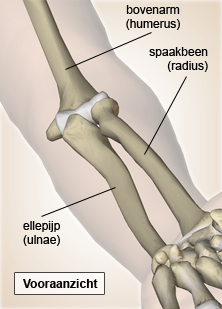

Elleboog